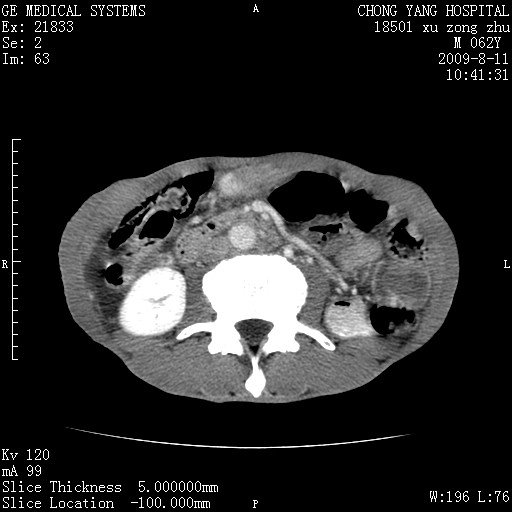

以下是引用杀毒软件在2009-8-11 16:35:00的发言:[br]肝内胆管扩张局限于左叶,胆管内有结石伴肝外胆管结石,胆管壁增厚呈弥漫性并发腹腔积液,胰腺边界模糊。[br][br]考虑---胆总管及肝内胆管结石继发胆管炎及胰腺炎,左肾下极囊肿,腹水。

以下是引用zjzjr在2009-8-11 17:35:00的发言:[br]肝内胆管扩张局限于左叶,胆管内有结石伴肝外胆管结石,胆管壁增厚呈弥漫性并发腹腔积液。[br][br]考虑---胆总管及肝内胆管结石继发胆管炎,左肾下极囊肿,腹水。